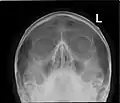

![]() Paranasal sinuses seen in a frontal view | |

Paranasal sinuses radiograph (occipitofrontal)